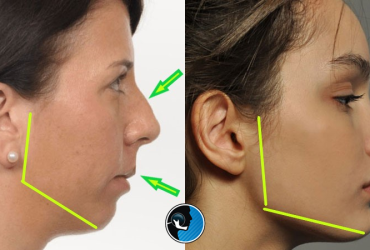

درمان کوچک بودن فک

درمان کوچک بودن فک: راهکارهای نوین اصلاح فک بالا و پایین کوچک بودن فک یکی…